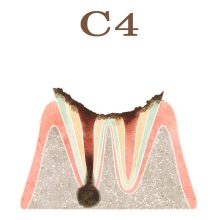

「C」とは歯科検診でよく使われる記号で、”caries”(カリエス、つまり虫歯)の頭文字を表します。「C」の後につくアルファベット(O)や数字(1,2,3,4)は、虫歯の進行具合を示します。

・C4(シーフォー): 虫歯が進行し、歯のほとんどを失い、根っこだけが残った状態を指します。この段階では、虫歯によって歯の組織が深刻に損傷し、復元が困難な状況になっています。そのため、早期の虫歯の発見と治療の重要性が強調されます。定期的な歯科検診や適切な口腔衛生の維持は、虫歯の予防と進行の防止に役立ちます。